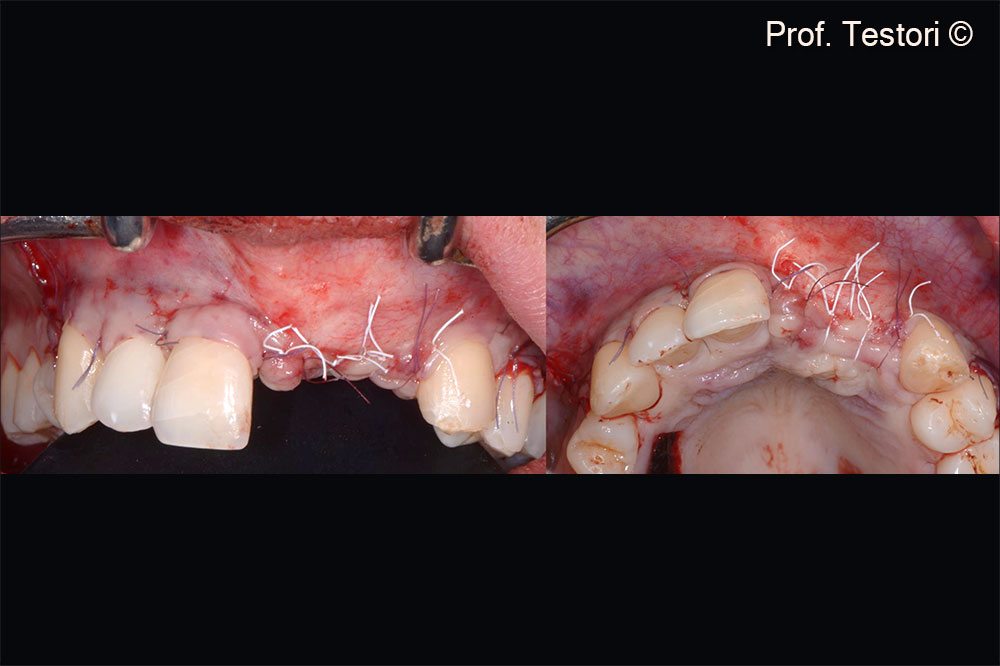

Soft tissue flaps are sutured